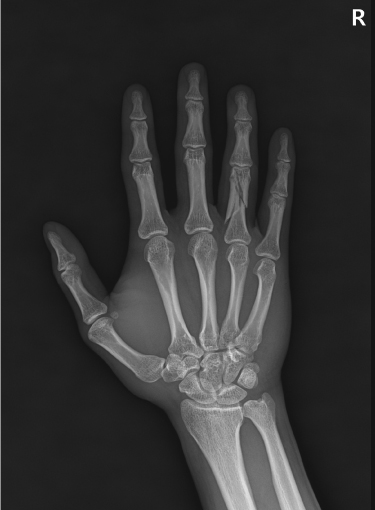

손목 골절 및 손가락 골절

대부분 손을 짚고 넘어지면서 발생하는 골절이고 다치면서 손등 쪽 뼈가 심하게 분쇄되는 경우가 많습니다.

골절 초기나 아니면 지연성으로 골절편이 손등 쪽으로 휘어져 변형이 발생하기 쉽습니다.

손목&손가락 골절에서 발생하는 문제점

□ 골절을 유합 시키기 위해 장기간 깁스를 할 경우 손목 관절이나 손가락 강직 발생

□ 손목 관절을 정확히 정복하지 못할 경우 외상성 관절염 발생 위험 높음

손목 골절

2023.01.04

2023.03.20